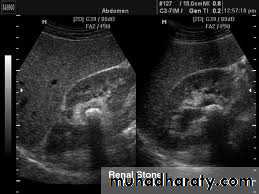

2-Stones larger than 5 mm are easily seen on US but smaller ones may be missed.

-They produce intense echoes (hyperechoic) and cast acoustic shadows.

1-Dilatation of the P.C.S. appears as multilocular fluid collection within central echo complex.-With more severe distention, dilated calyces appear as Multiple cysts but communicating with each other unlike true cysts.